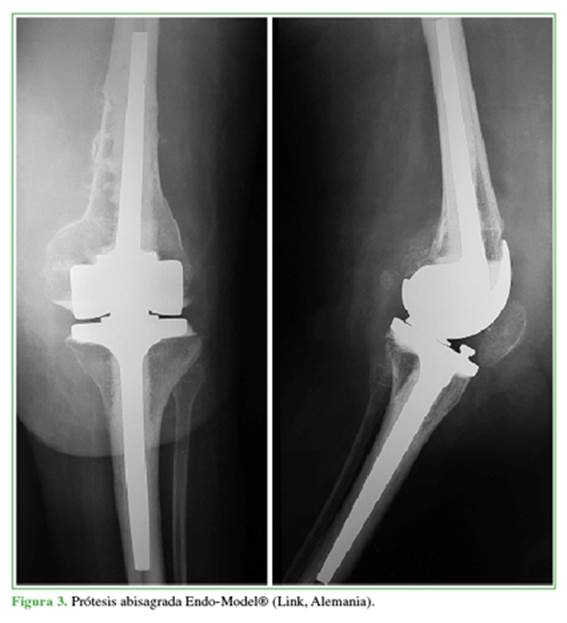

En todos los casos, se utilizó una prótesis abisagrada rotatoria (Endo-Model®; Link, Alemania) (Figura 3), excepto en dos con fuerza del cuádriceps antigravitatoria a quienes se les colocó una prótesis estabilizada posterior (Scorpio ®, Stryker, EE.UU.).